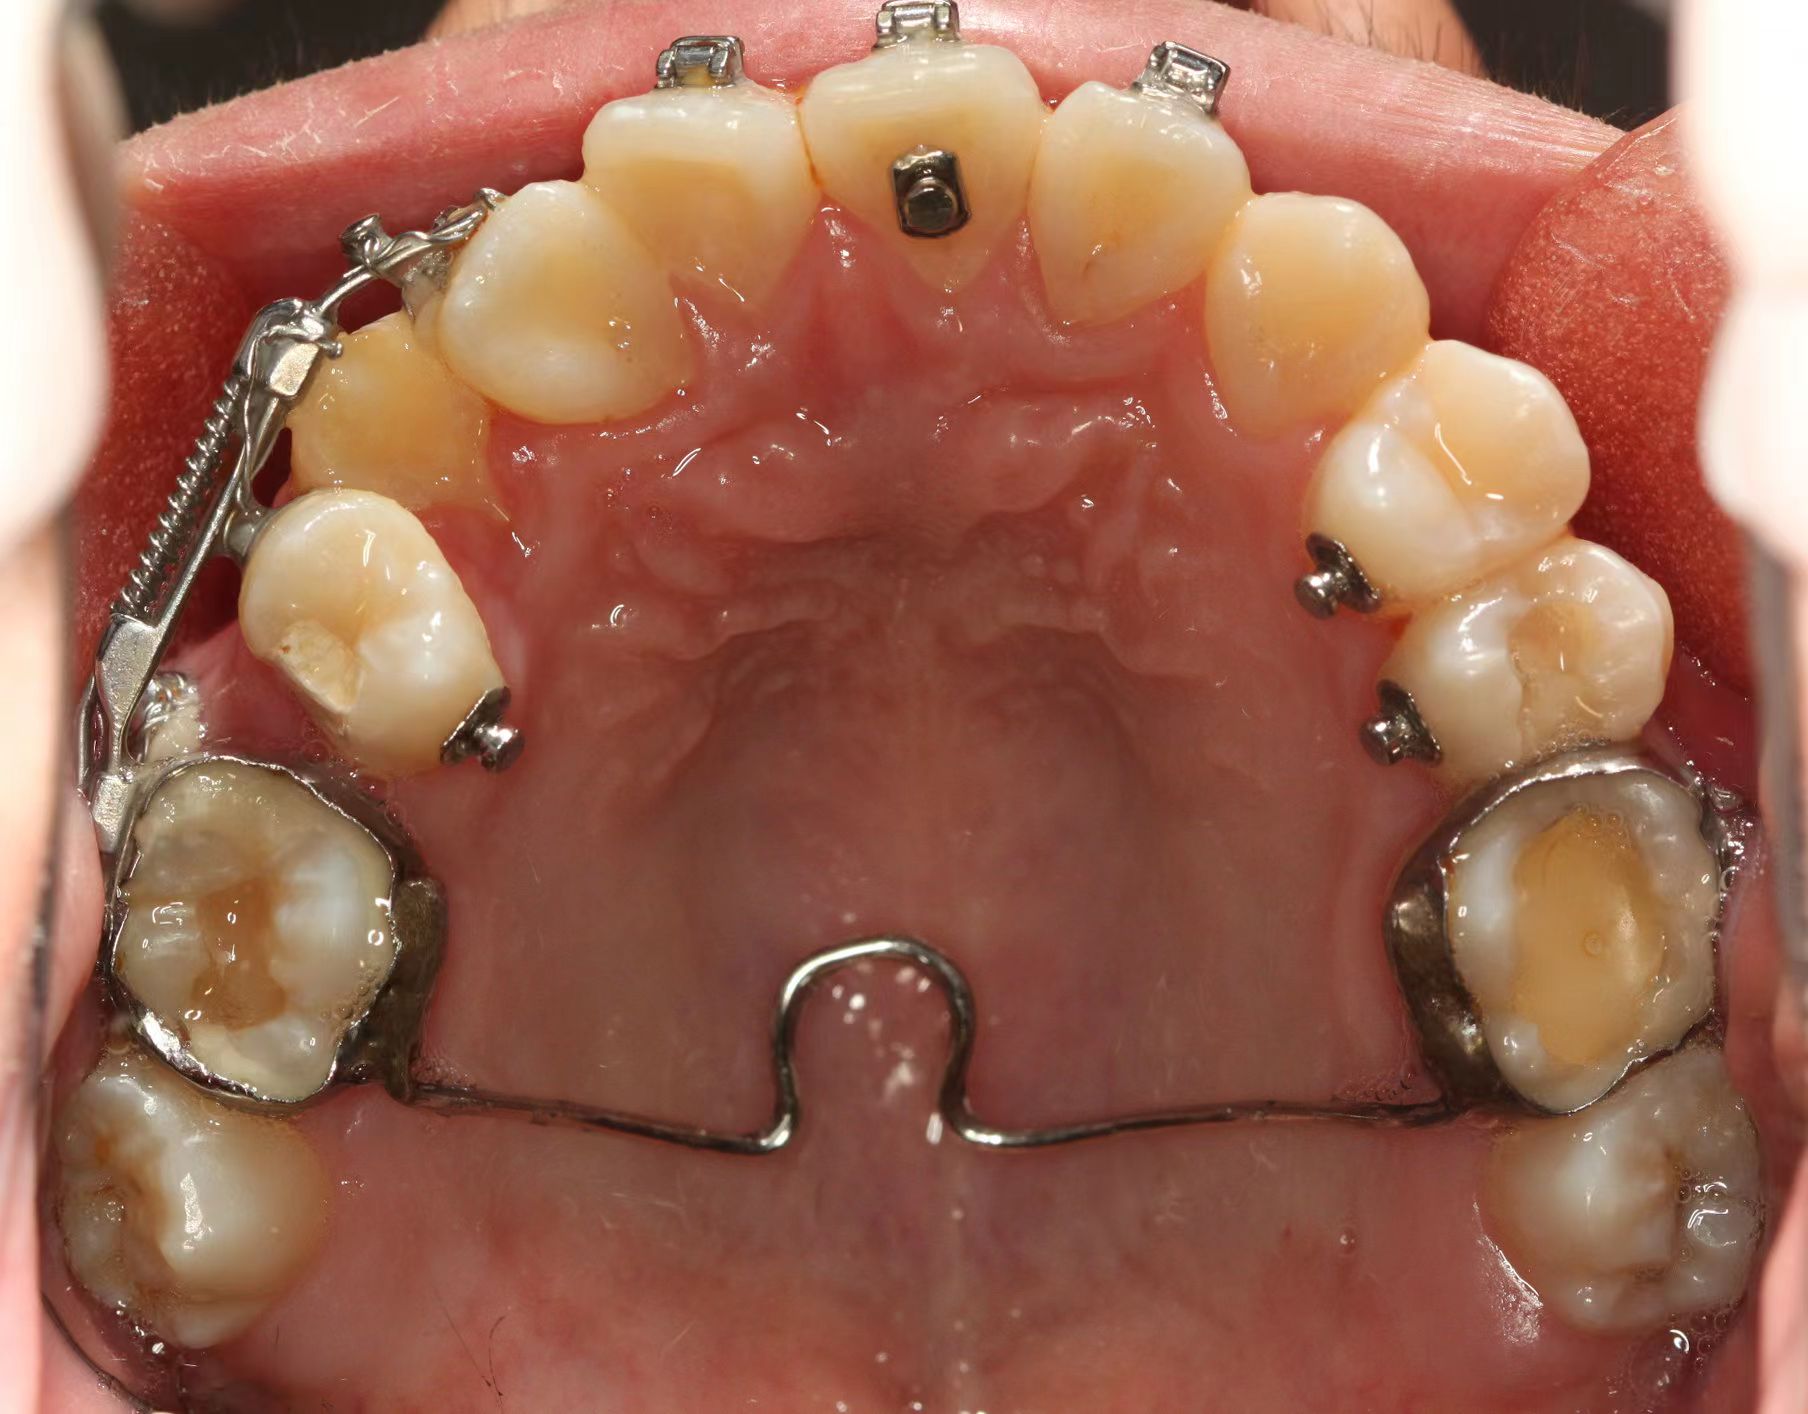

情况:不接受外科手术,在当地做了1年半的矫治,遇到困难无法进行。由外地正畸同行推荐来上海寻求非手术矫治的二手病例。武广增老师接收时的错合畸形情况,呈现严重的骨性反合偏合及侧方开合(图1-图10)。由于推荐其去口腔医院接受正颌外科手术遭到拒绝,武广增老师通过专业的检查、分析,制定一套详细的治疗计划,采用了磨牙推进器技术、武式辅弓技术等特色正畸手段获得明显效果(图2-1~图2-9)。治疗结束后也拍摄了相关照片(图3-1~图3-9)。

矫治效果

图2-5